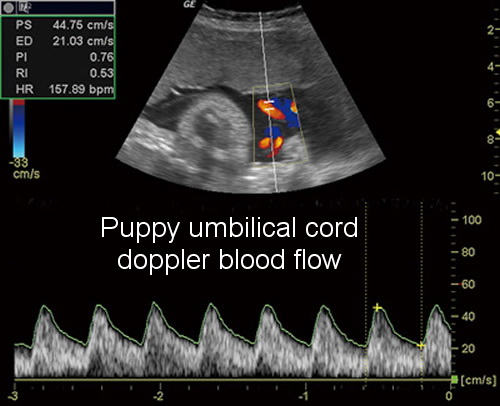

With ultrasound, we are able to do studies as simple as pre-natal puppy checks up to advanced cardiac imaging. All of our cardiac studies are interpreted by a Board Certified Cardiologist and most abdominal studies are read by a Board Certified Radiologist. This gives us the most competent and complete information from the most competent experts. The images are sent over the internet to the appropriate specialist who may be located anywhere in the United States. There are some cases where we will refer you directly to a specialist depending on the type and severity of the illness however, in most cases, providing ultrasonography here offers an efficient, convenient and cost effective means of getting diagnostic questions answered quickly - often while you wait.